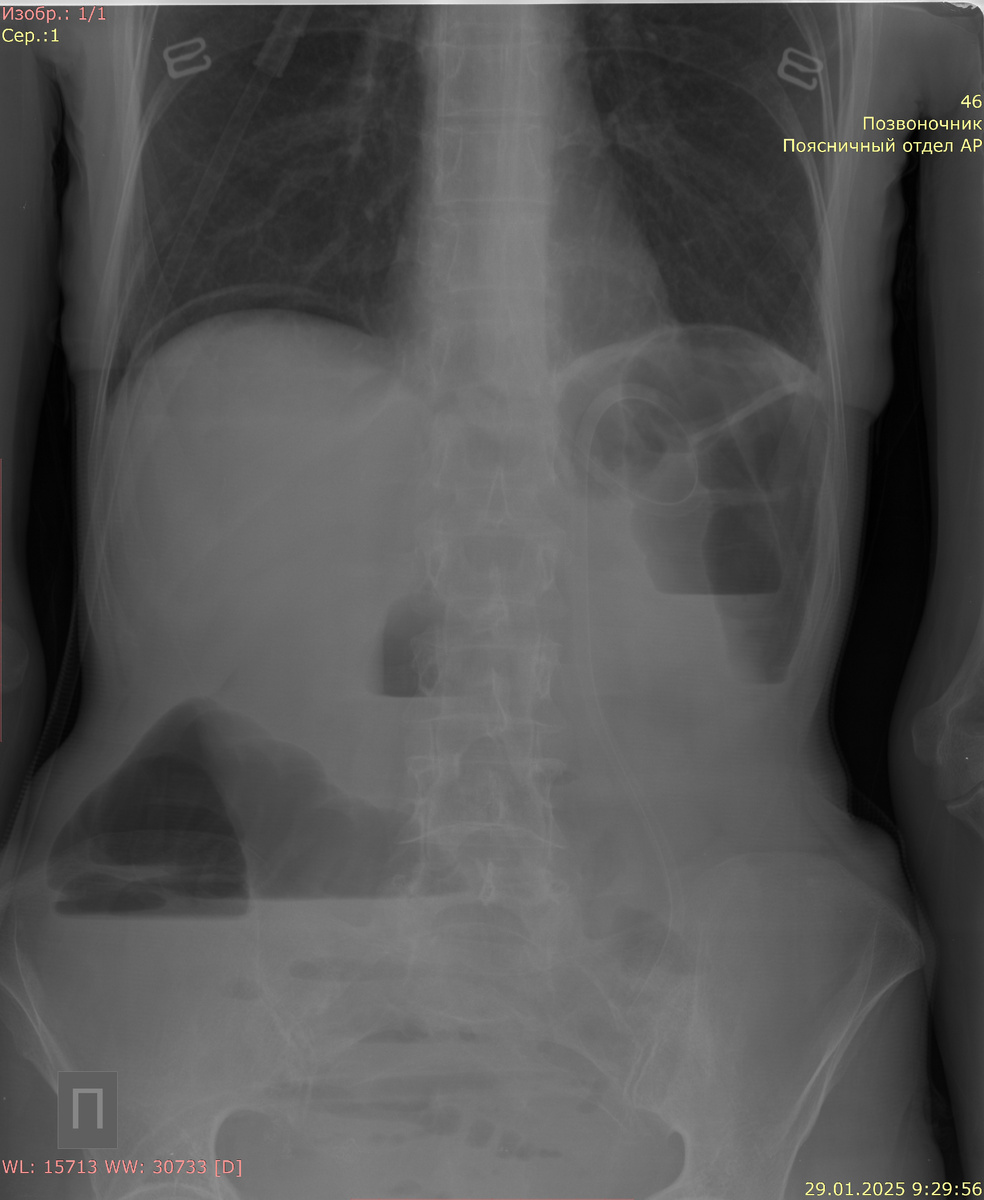

Рентгенологические исследования являются первыми методами, к которым обращаются при подозрении на толстокишечную непроходимость. Они помогают определить наличие или отсутствие этого состояния. На рентгенограммах живота без контраста специалисты используют принцип "дважды обдумать", что подразумевает внимательное исследование общей картины. Врачи обращают внимание на наличие уровня жидкости, расширение кишечных петель, а также на наличие свободного воздуха в брюшной полости, что может указывать на возможную перфорацию кишечника.

На рентгенограммах специалисты могут заметить общие признаки, такие как расширение дистальных отделов кишки и сужение или отсутствие контрастирования в более проксимальных участках. Эти находки позволяют врачам оценить уровень непроходимости и выявить потенциальные причины ее возникновения.

Ширина толстой кишки боле 60 мм - непроходимость.